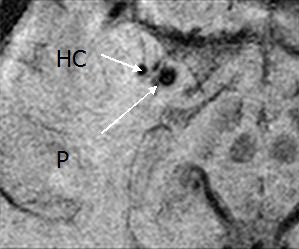

![]() |

| Above and below, susceptibility weighted imaging technique shows bleeding in the hippocampus (HC) and the adjacent putamen (P) and globus pallidus (GP), suggesting why the patient had short-term memory loss. Images courtesy of the department of radiology at Wayne State University. |